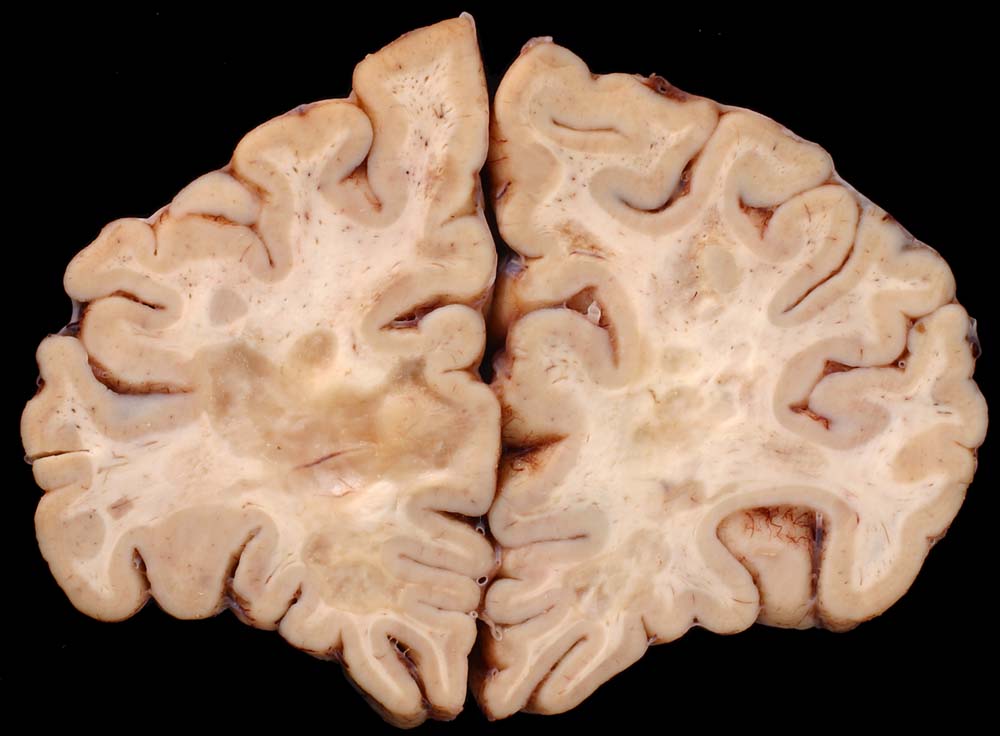

Entmarkungsherde bei Multipler Sklerose

Fleckförmige Grauverfärbung des Marklagers ( Entmarkungsareale).

Chronische und aktive Entmarkungsareale in der weissen Substanz (beidseits, periventrikulär betont).

Diagnose einer multiplen Sklerose vor 12 Jahren. Paraparese der Beine. Neurogene Blasenentleerungsstörung. Seit einem Jahr deutliche neurologische Verschlechterung.